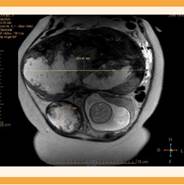

Se dispuso de una resonancia magnética nuclear para planeación quirúrgica en la que se encontró un leiomioma gigante subseroso, que emergía del fondo uterino, con datos de proceso degenerativo, de 350 x 180 x 172 mm, con compresión directa al útero gestante, las vísceras abdominales y la caja torácica. Se identificó otro leiomioma subseroso, con componente intramural hacia la cara lateral derecha de 105 x 80 mm de diámetro. El tercer leiomioma subseroso e intramural se ubicó en la cara anterior y el fondo uterino de 70 x 70 mm. Ninguna de las lesiones afectaba la inserción placentaria, pero los dos leiomiomas con componente intramural se observaron a 10 y 50 mm de la bolsa amniótica. Figuras 2y3

Figura 2 Resonancia magnética nuclear abdomino-pélvica, corte coronal, que muestra los dos leiomiomas en su diámetro mayor. También se observa la disposición de la cabeza fetal y de la placenta intrauterina